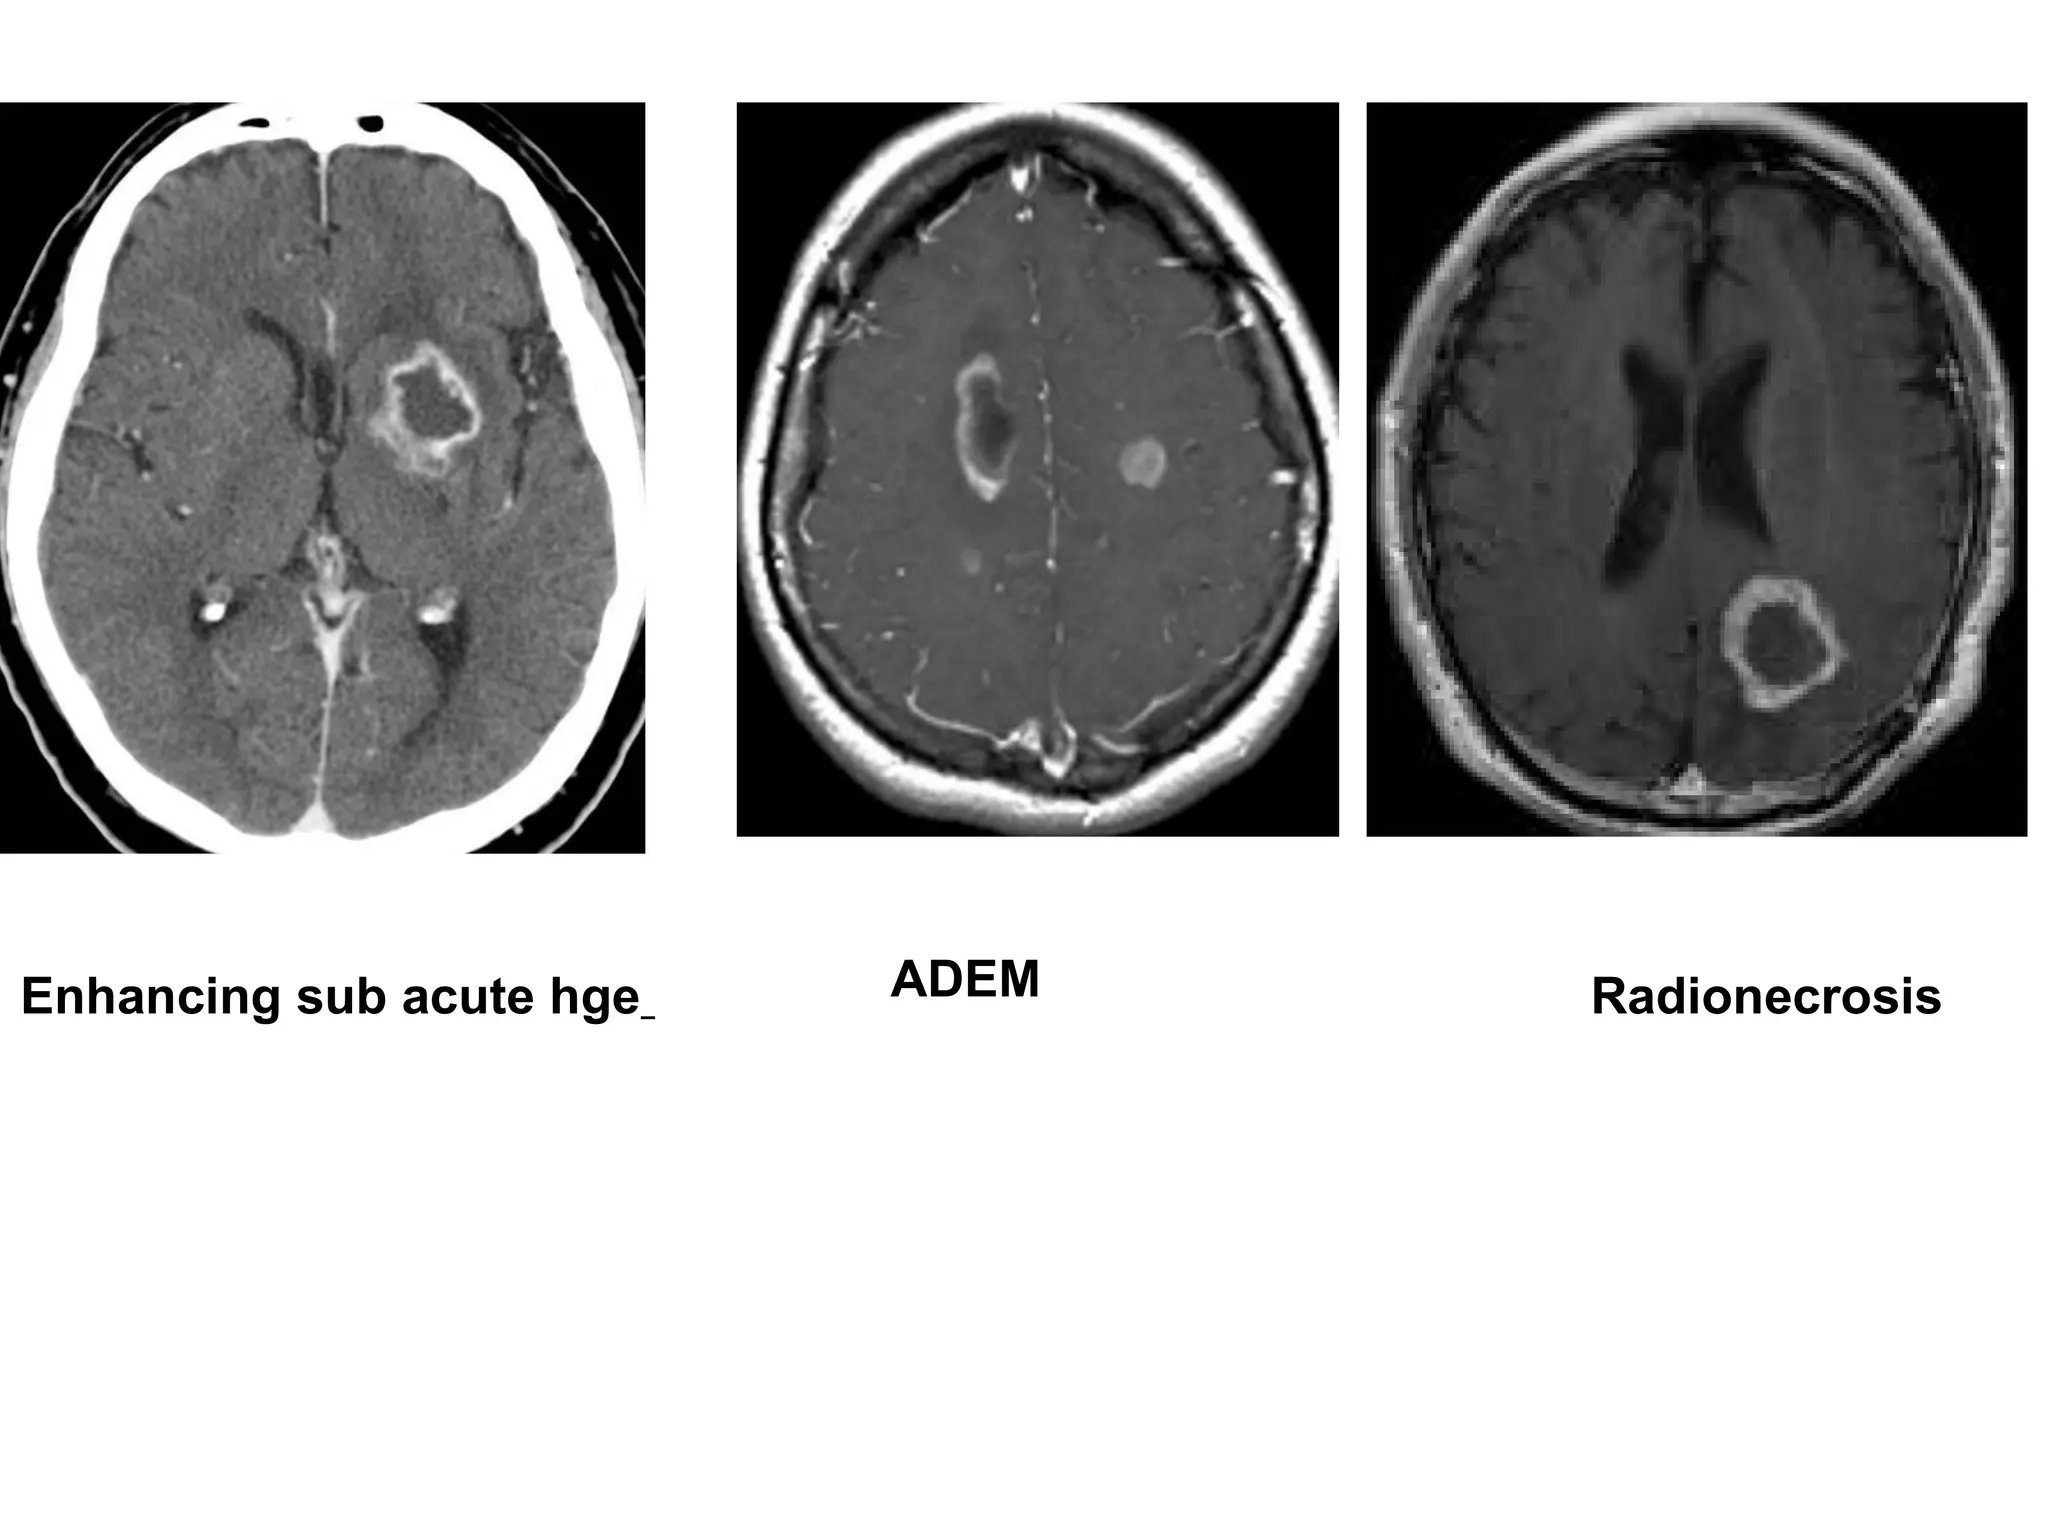

Enhancing sub acute hge ADEM Radionecrosis

Enhancing sub acutehge ADEM Radionecrosis